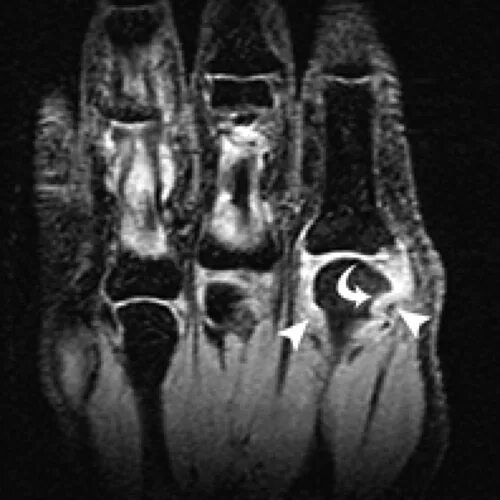

Мрт суставов кемерово